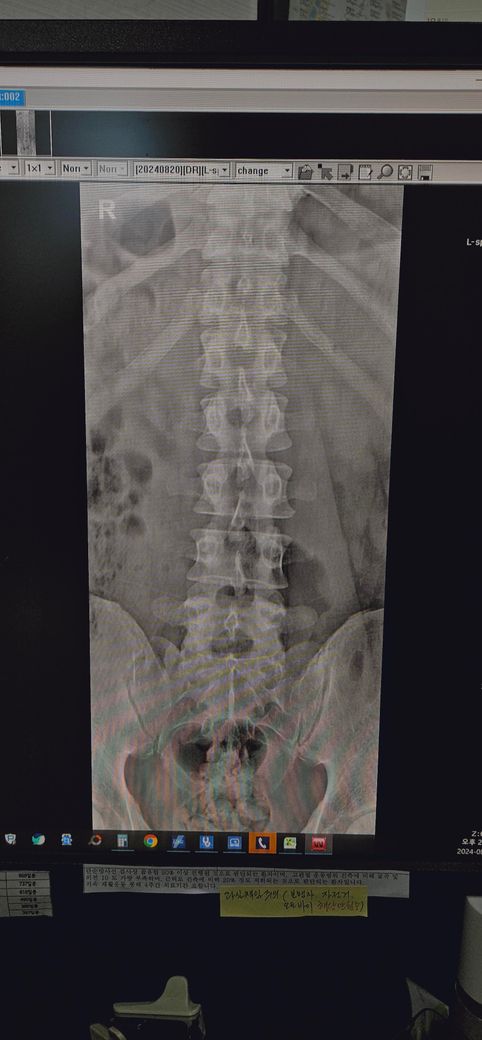

일자 허리인지 봐주세요(엑스레이 첨부)

정상허리로 봐야하는지 일자허리로 봐야하는지 궁금 합니다.

그리고 척추측만증이나 골잔 좌우 비대칭도 한번 봐주시면 좋겠습니다

교정이 필요한 수준인지

• 1번 째 사진

사진으로 보아서는 정상 허리에 비해 허리의 만곡이 완만해져 있으며 척추도 약간 휘어져 있으며 골반도 틀어져 있는 것 같이 보입니다.

측만은 거의 없고 골반도 이정도면 크게 비대칭이라고 하긴 어렵겠습니다. 따로 교정이 필요할것 같진않고 다만 골반 이하로 어디 불편감이 있거나 통증이 있다면 치료를 해볼순 있겠습니다.

허리를 전만 커브고 약간 적은 편이라 경도의 일자 허리 정도라고 볼수는 있겠으나 심해보이진 않고 요추전만 운동 해주고 코어운동 및 중둔근 위주 운동해주면 충분할것 같습니다.

측만증으로보이지는않지만 허리커브가 약간 소실되어있고 골반의 불균형도있는걸로보이는데요 지금당장은 큰문제는 아닐수있지만 지속적으로 자세적인불균형이나 안좋은습관 ,근육의 불균형이 생긴다면 후에 불편감이생길수도있으니 지금부터 관리하는것이 중요합니다

척추측만증도 없고 골반 비대칭도 지금 사진으로 정확한 판별은 어렵지만 치료가 필요한 정도의 상황이 아니라고 예상됩니다.